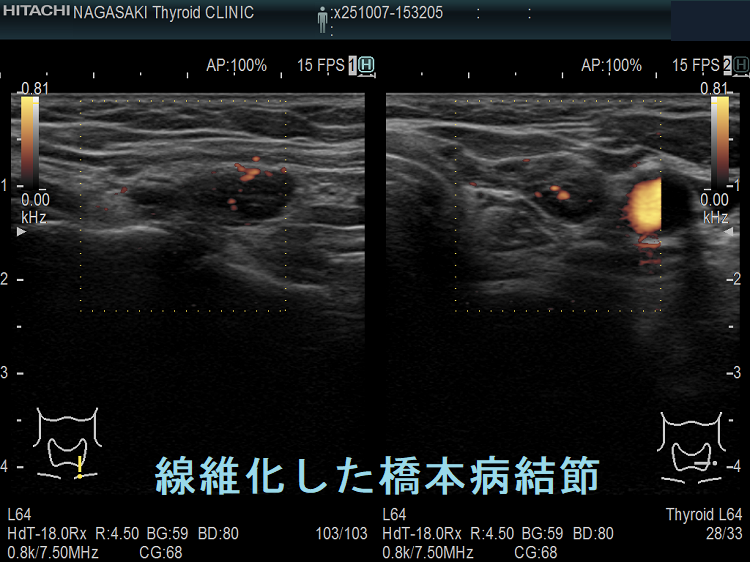

橋本病(慢性甲状腺炎)ではリンパ球浸潤に伴う炎症から濾胞細胞の好酸性変性[好酸性細胞(Hürthle細胞,ハーテル細胞)]・過形成、浮腫、線維化で結節性病変を形成[結節性橋本病(橋本病結節)]。病理学的に腺腫様甲状腺腫・腺腫様結節と同じで、橋本病(慢性甲状腺炎)を基盤とする腺腫様甲状腺腫・腺腫様結節。超音波(エコー)検査では内部が極めて低エコーのため甲状腺癌、甲状腺原発悪性リンパ腫と鑑別必要。細胞診では好酸性細胞、リンパ球集簇、炎症性多核巨細胞を認め、甲状腺乳頭癌ワルチン腫瘍型、通常型甲状腺乳頭癌・亜急性甲状腺炎と鑑別要。

橋本病(慢性甲状腺炎)では、リンパ球浸潤に伴う炎症から、濾胞細胞の好酸性変性・過形成、浮腫、線維化などの変化で結節性病変が形成されます[結節性橋本病(橋本病結節)]。病理学的には腺腫様甲状腺腫・腺腫様結節と同じ事で、橋本病(慢性甲状腺炎)を基盤とする腺腫様甲状腺腫・腺腫様結節になります。

橋本病リンパ球浸潤、橋本病結節 どちらともとれる見え方です。境界がはっきりしているので橋本病結節とも言えるし、炎症性変化が主体なので橋本病リンパ球浸潤とも言えます。